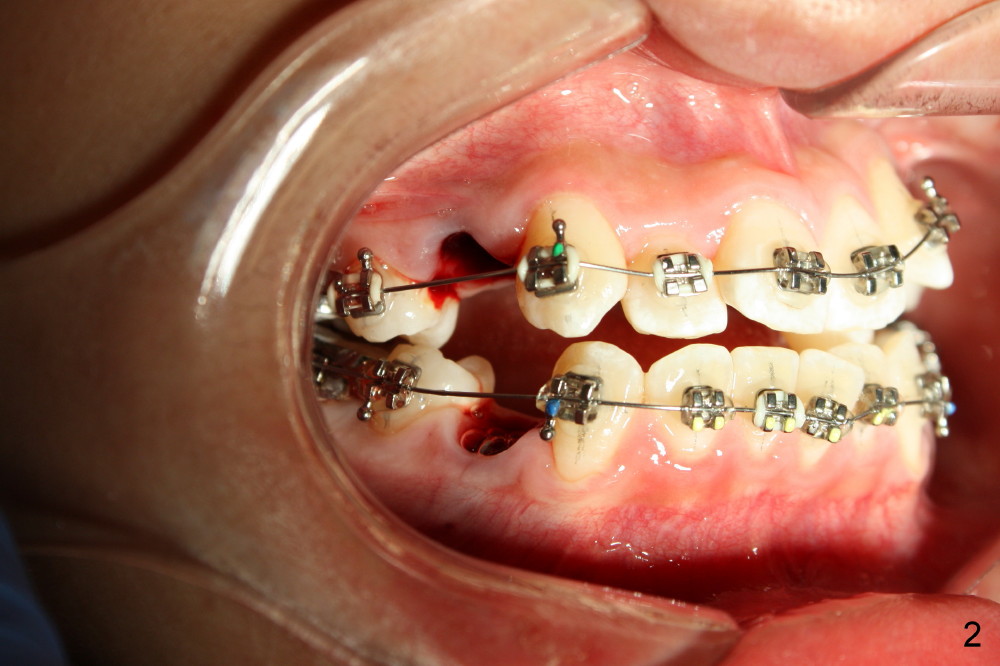

David, 16 years old, has severe crowding, midline deviation (Fig.1: dashed lines), and UL2 complete blockout (Fig.3: 2). Orthodontic treatment starts with extraction of four of the 1st bicuspids (Fig.2,3: .014 Niti).